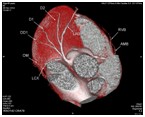

冠状动脉CT成像